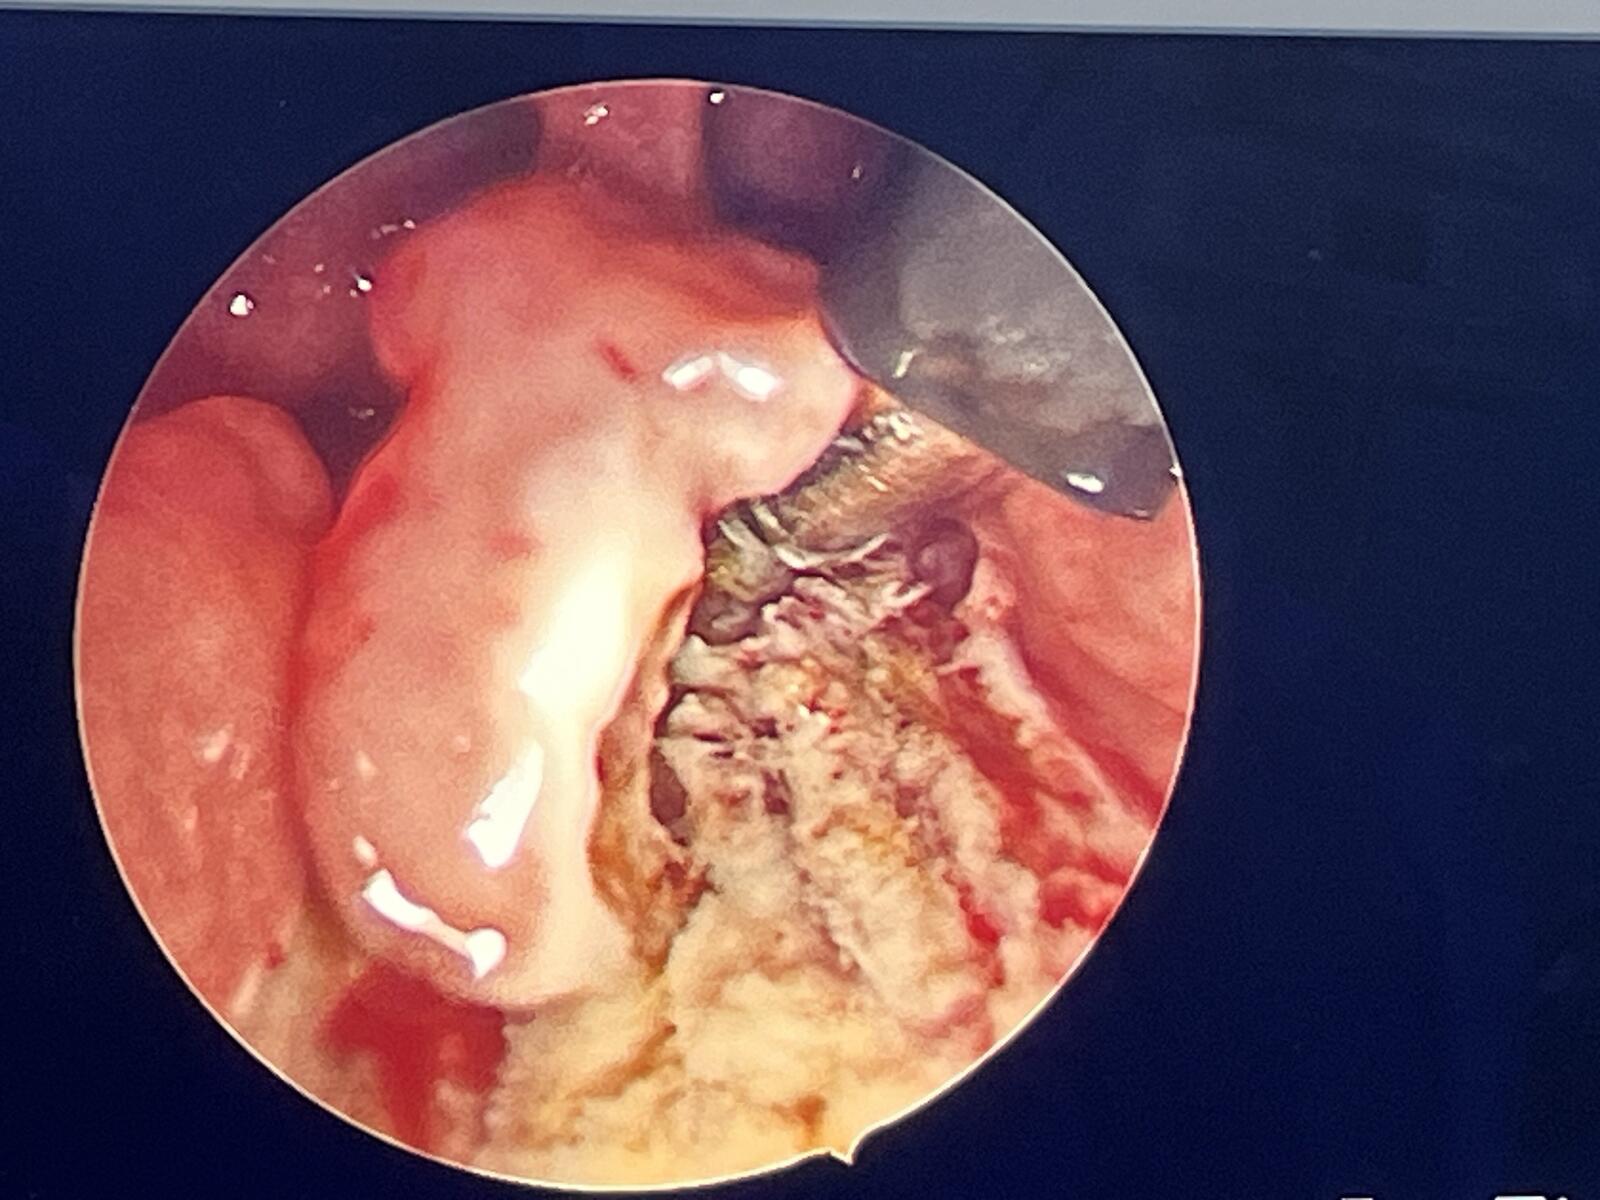

左扁桃体下极保留1/5

处理到位的软腭层面